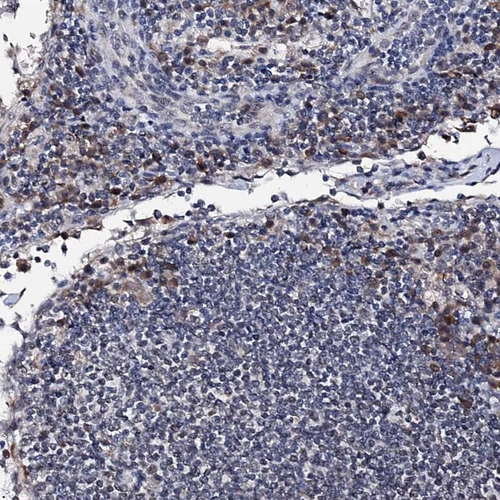

HPA038511

peroxisome proliferator-activated receptor gamma, coactivator-related 1

Anti-PPRC1 Antibody

Polyclonal Antibody against HUMAN PPRC1